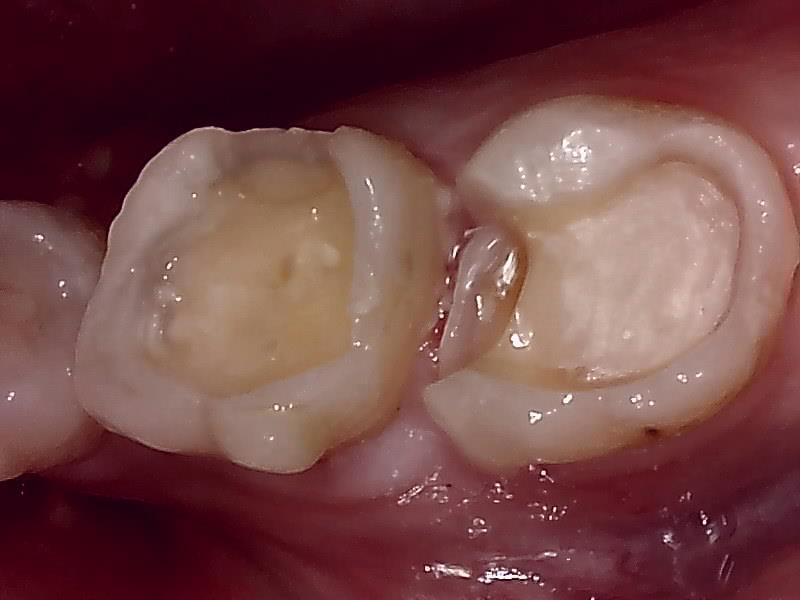

セラミックインレーの装着前の窩洞形成(写真)

仮歯の装着して近心歯肉の回復を待つ。

仮歯の装着後、歯肉の治癒期間は後1~2週間後程度になる。